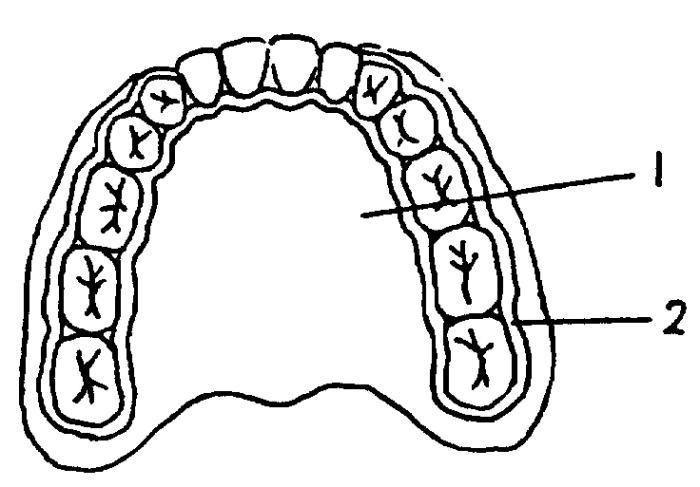

牙列不齐者由于口腔自洁作用较差,不整齐的牙之间更易藏污纳垢,牙菌斑和结石极易沉积导致牙龈肿胀反复发炎,时间一长牙周袋产生,牙槽骨破坏即牙周炎形成。